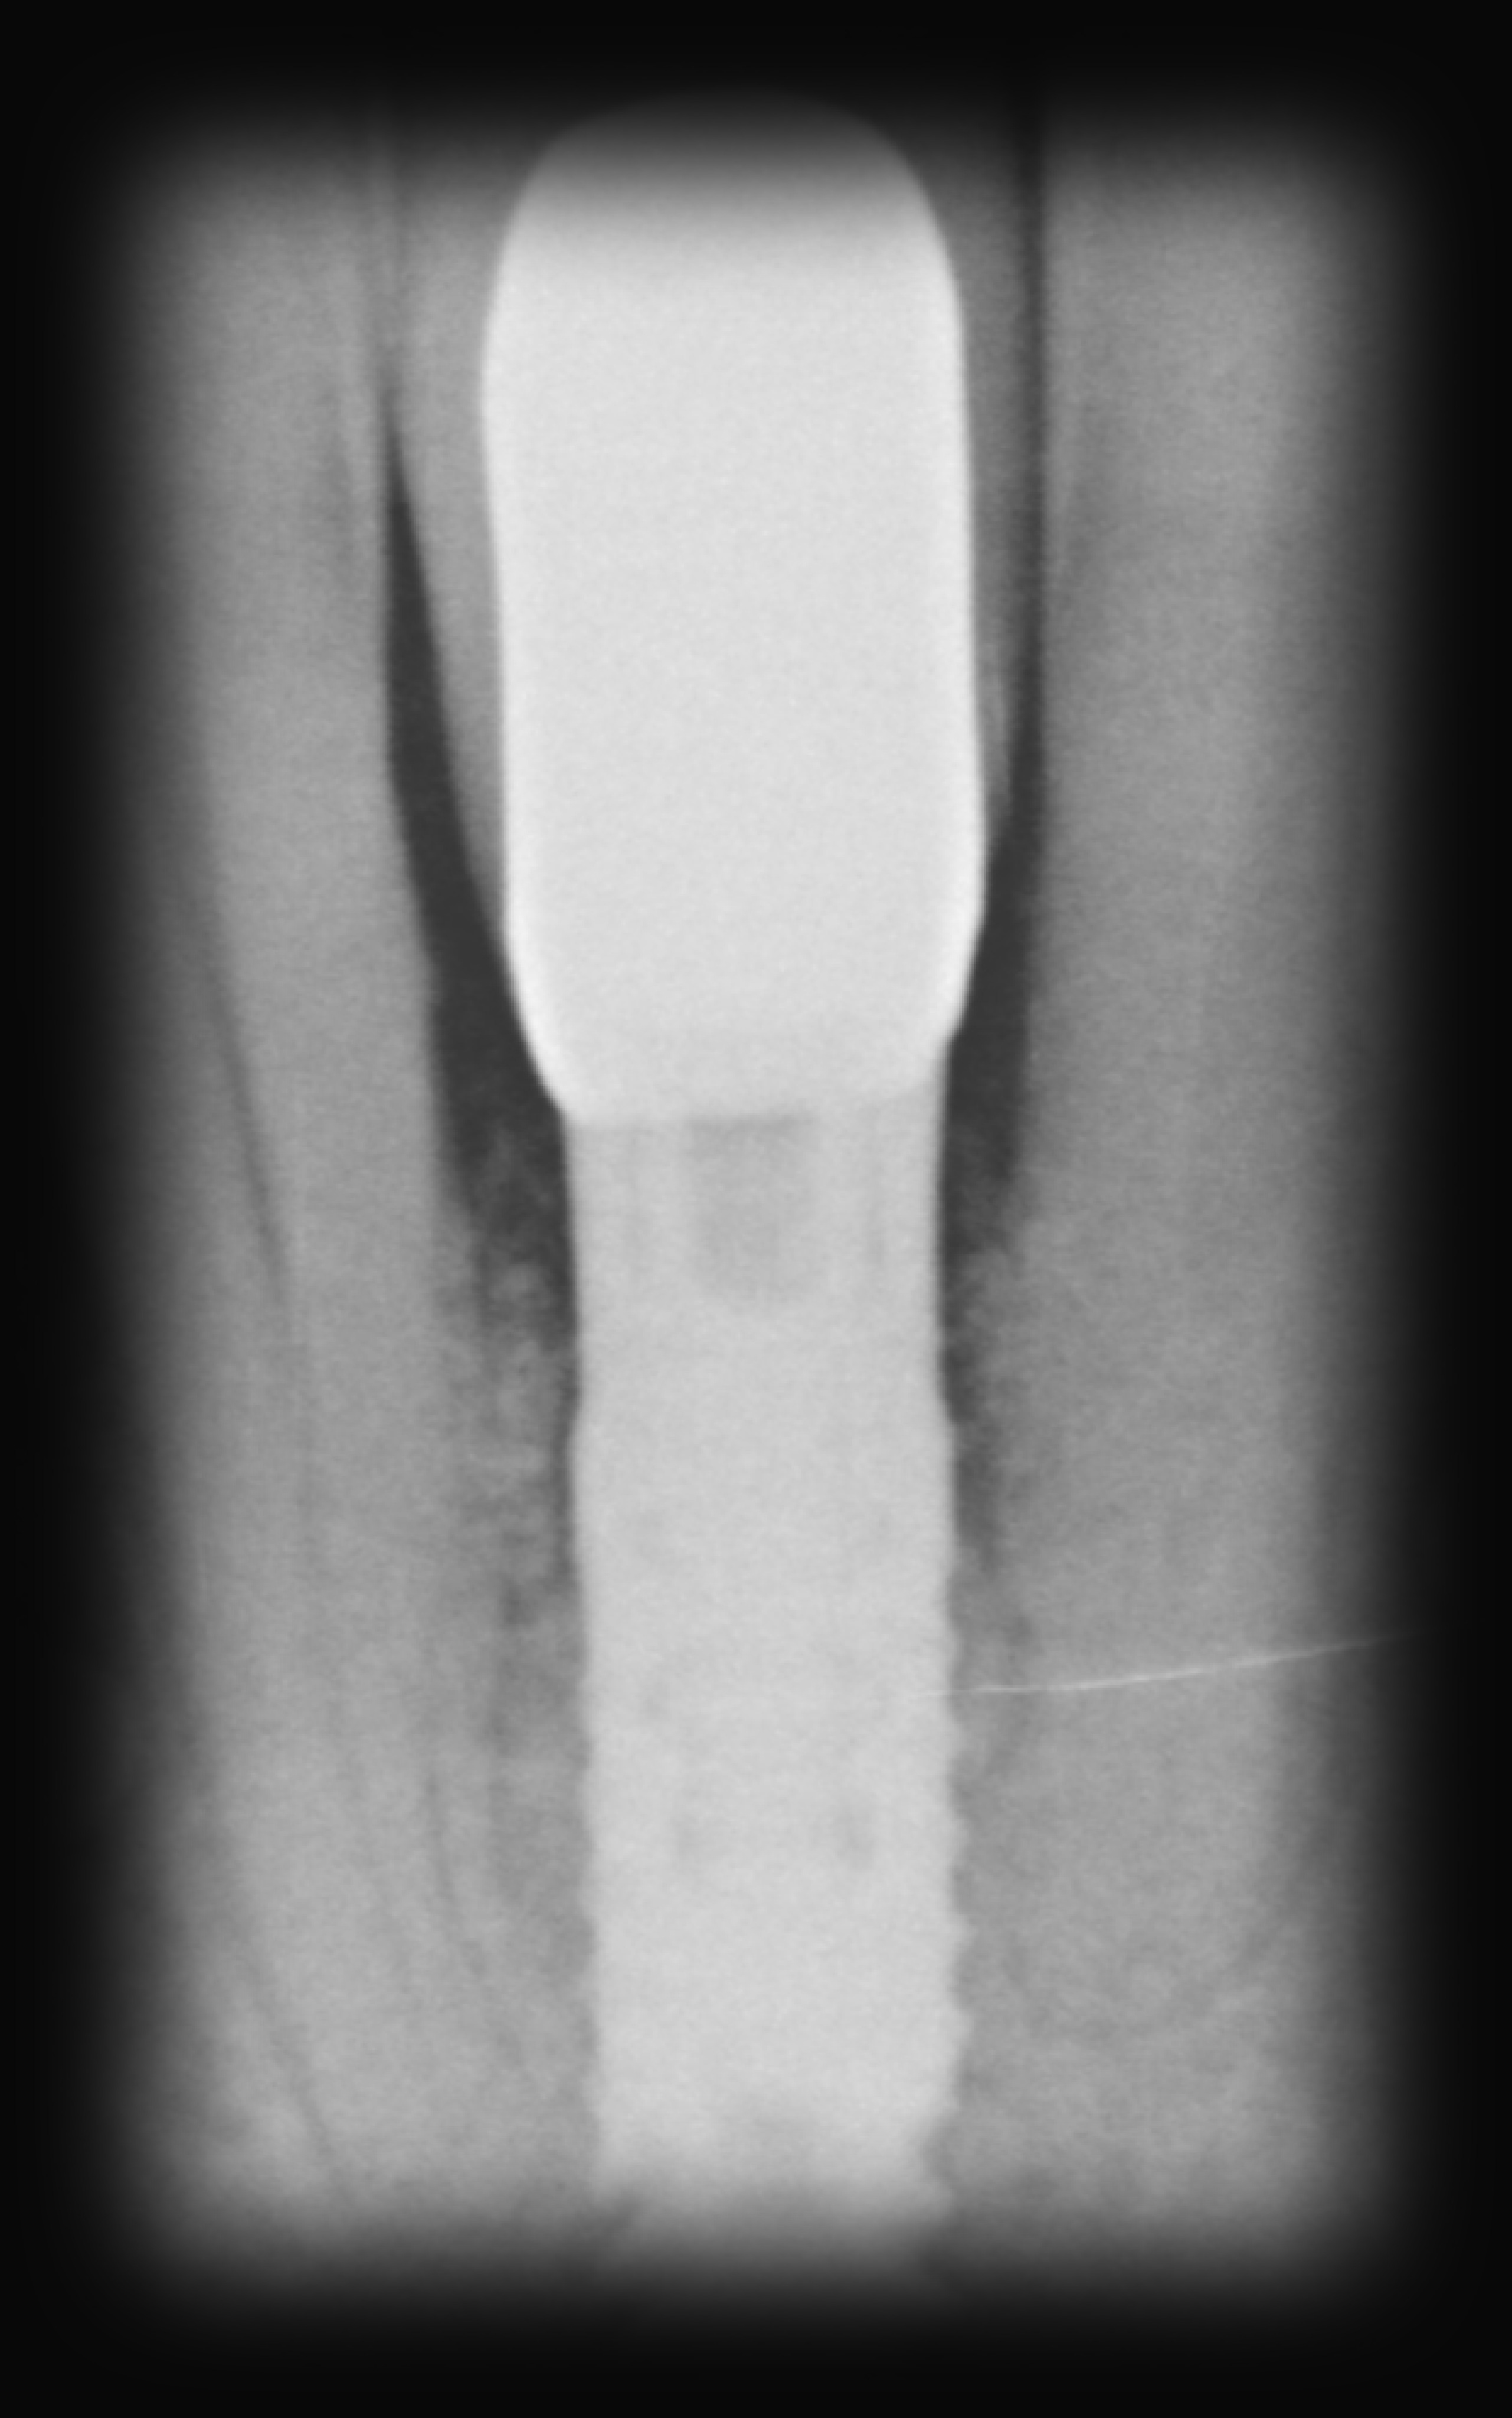

Eingliederung der Krone

Mein Fazit

Sieht super aus. Da ist die lange Zeit schnell vergessen. Es fühlt sich super an. Die Behandlung und Betreuung bei Unicare, 1A die Doc’s und die Mädels aller erste Sahne

VORHER

NACHHER

Die Arbeit ist seit 6 Jahren beständig